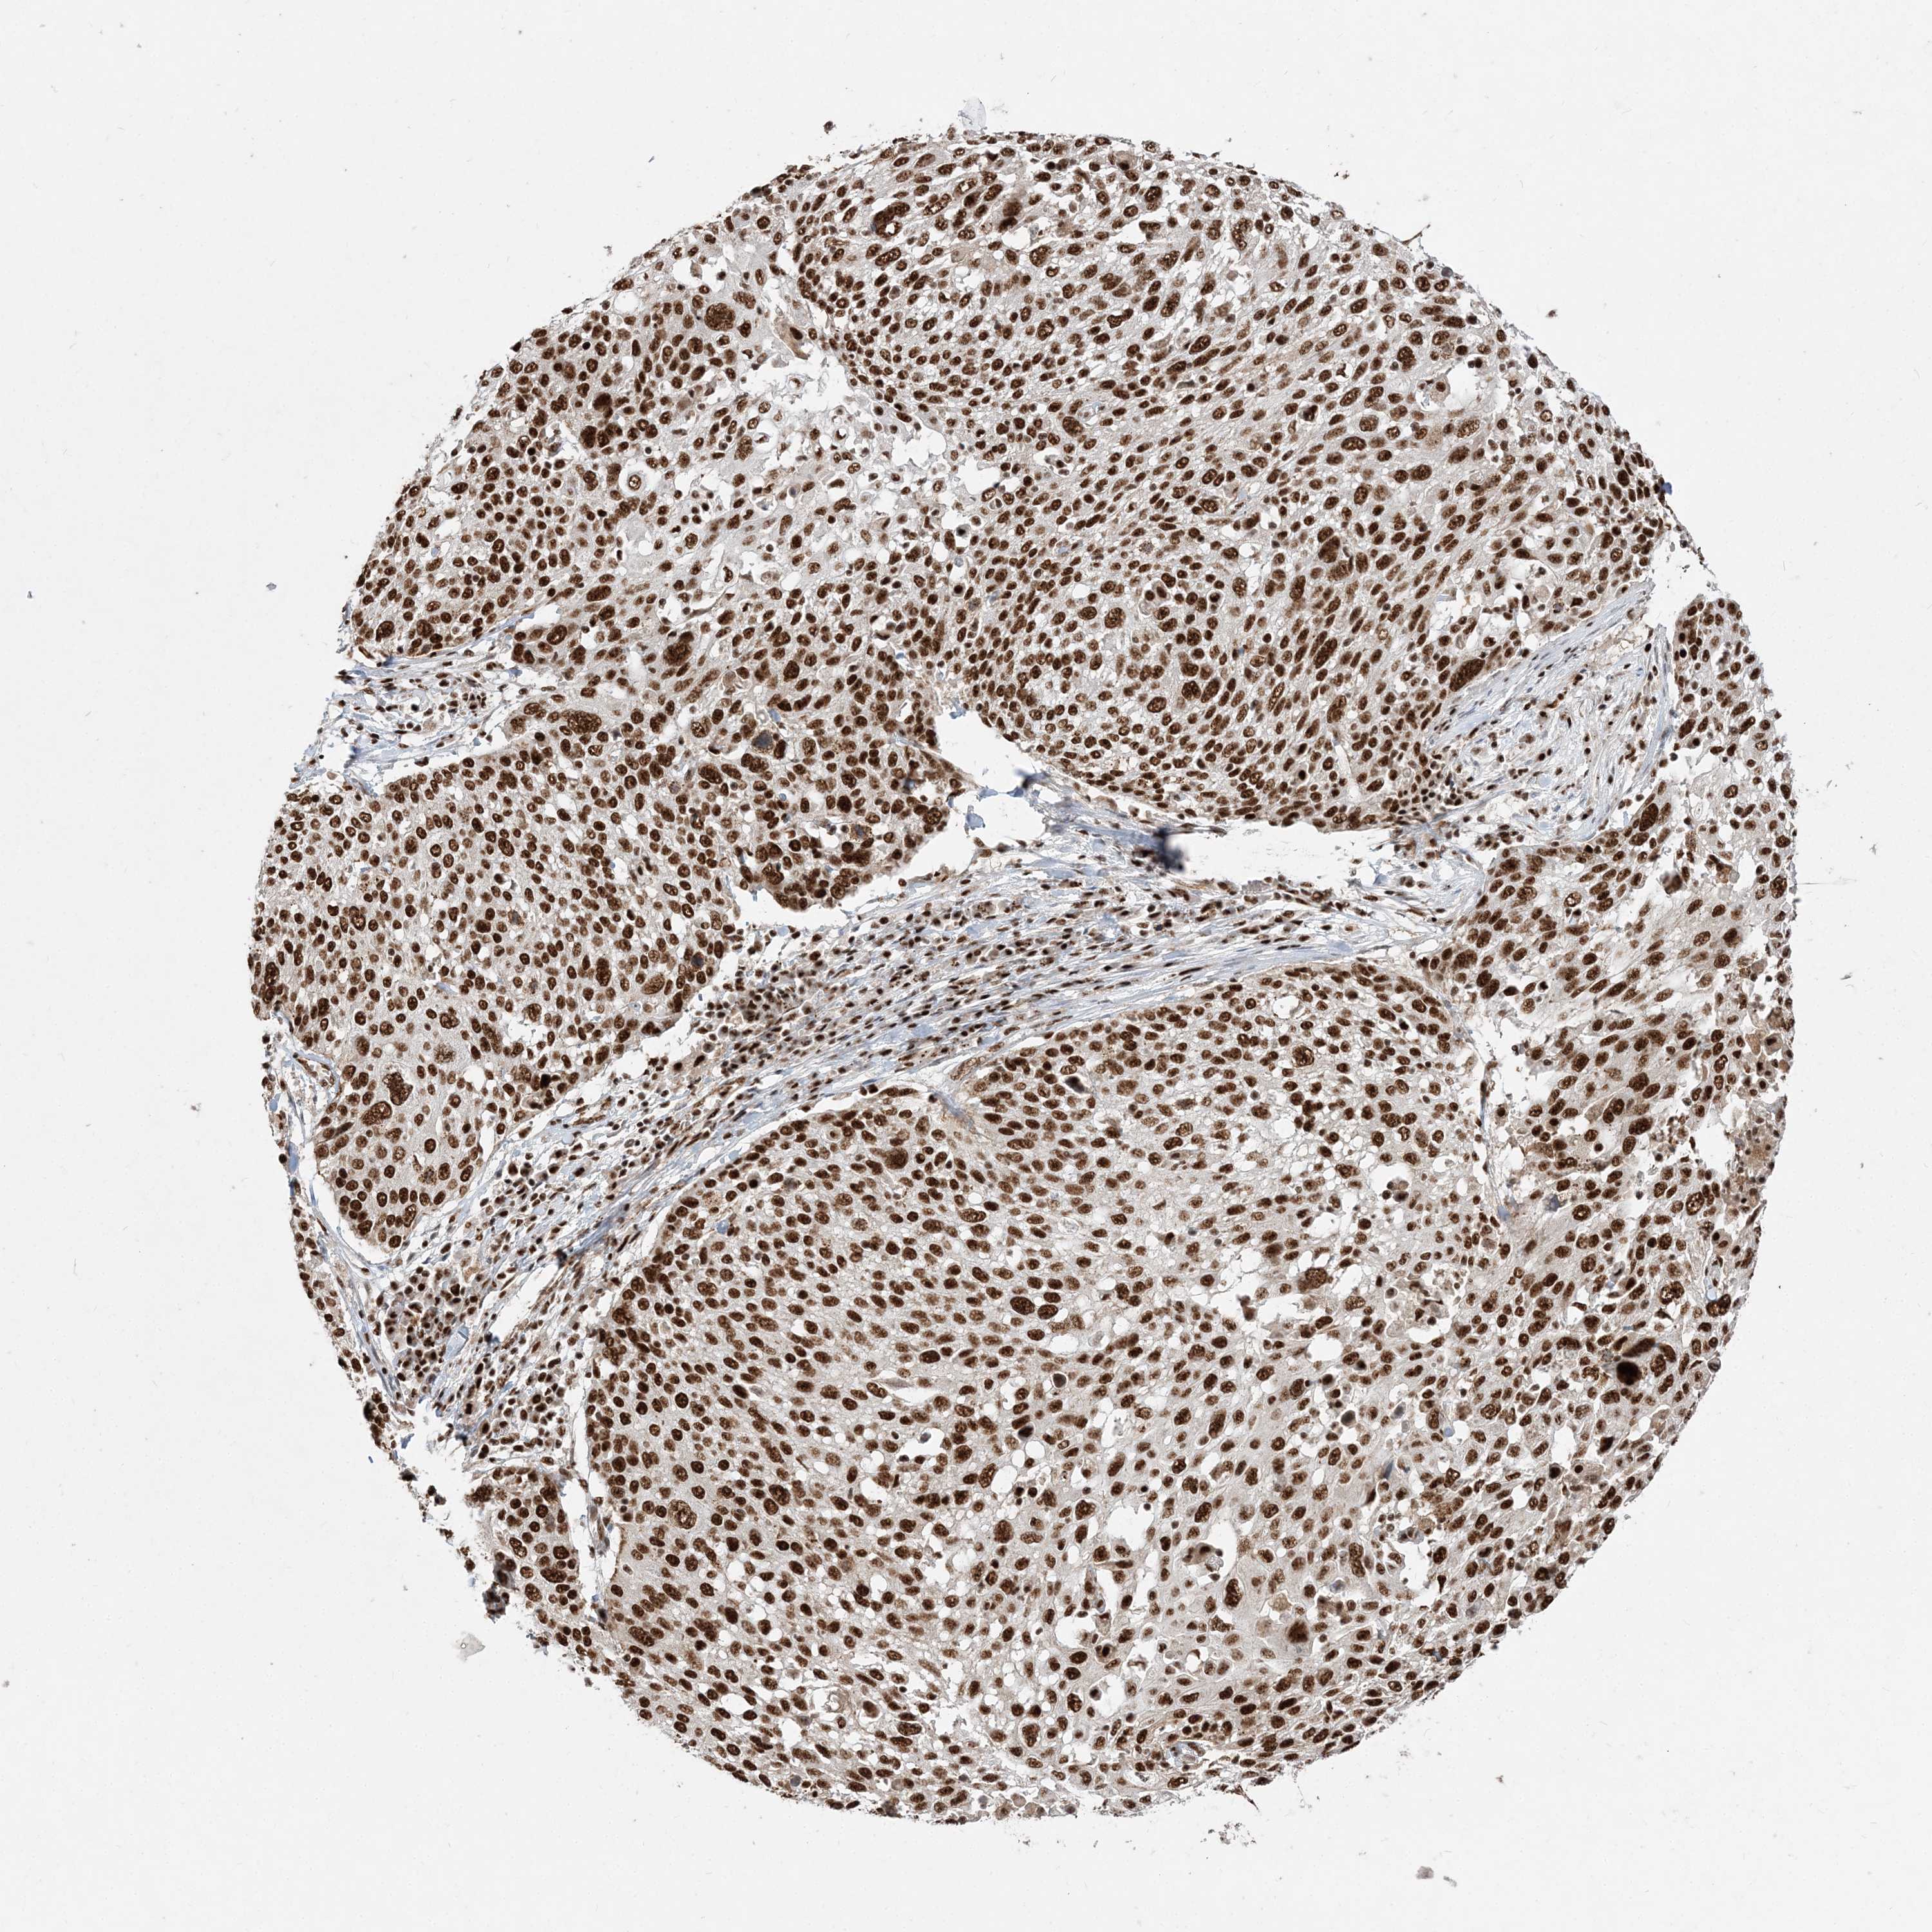

RBM17